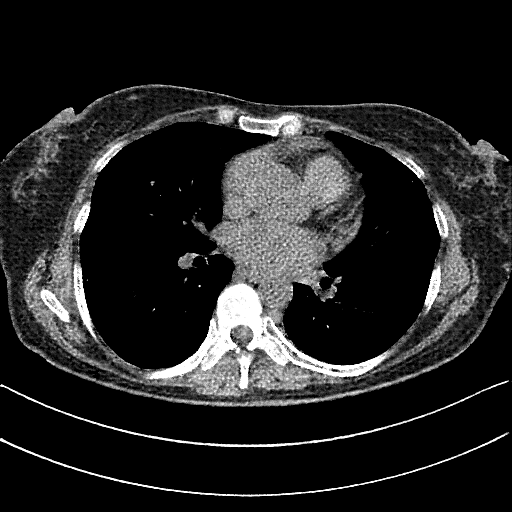

Generated VENOUS CT scan (A→B translation)

Full window (WL 1023.5, WW 4095 β†’ Low βˆ’1024, High +3071)

Actual HU range: [-1024.0, 1512.9]

Lung window (WL -600, WW 1500 β†’ Low βˆ’1350, High +150)

Actual HU range: [-1241.2, 150.0]

Mediastinum window (WL 40, WW 400 β†’ Low βˆ’160, High +240)

Actual HU range: [-160.0, 240.0]